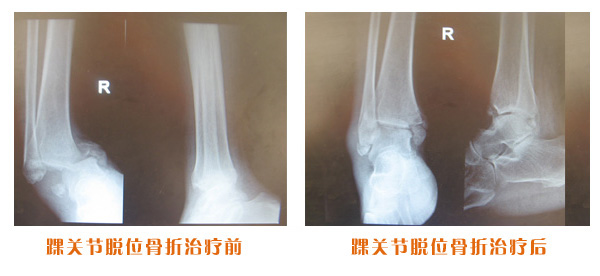

肥城市安駕莊梁氏骨科醫(yī)院是一所以梁氏手法正骨配合膏藥為特色的現(xiàn)代化專(zhuān)科醫(yī)院。

梁氏骨科術(shù)始創(chuàng)于清雍正年間,歷經(jīng)八代,至今已有三百年歷史。據(jù)1929年泰安縣志載“梁瑞圖先生,字增生,號(hào)蓮峰,安駕莊人,精岐黃并發(fā)明接骨,凡跌打車(chē)凡跌打車(chē)軋皮不破而碎骨者......【詳細(xì)】 |